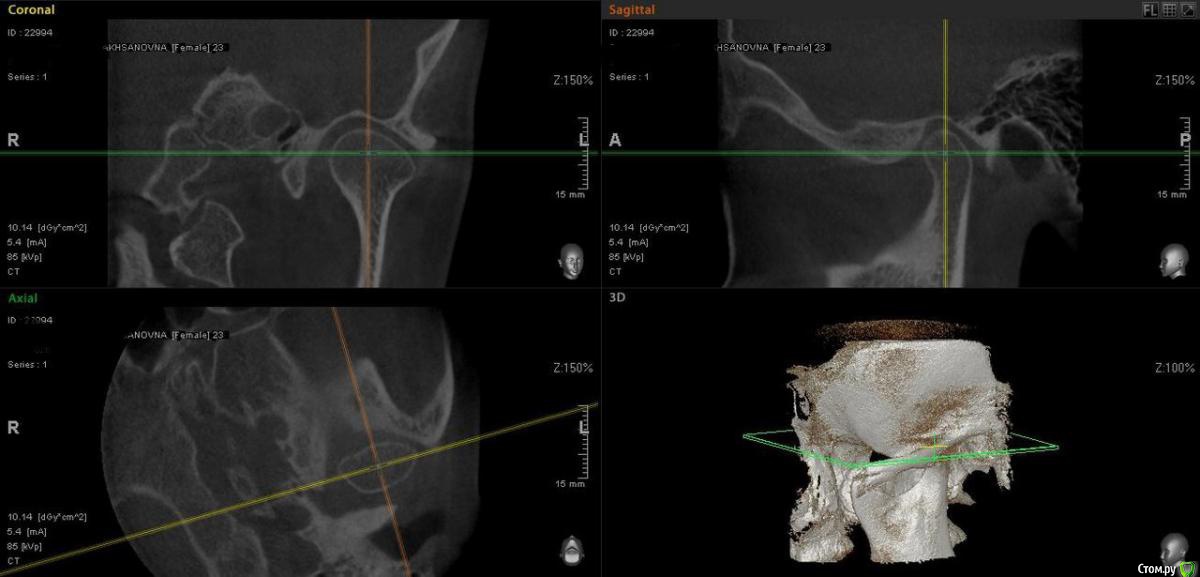

Айсылу Опубликовано 23 июля, 2015 Автор Поделиться Опубликовано 23 июля, 2015 Здравствуйте. Снова я с вопросом к Вам, уважаемые, ортодонты. Вот сделала такие снимки. Ортодонт из "Большого города" сказал, что суставные головки на месте и что выдвигать нижнюю челюсть нельзя. Расширять НЧ уже поздно, из-за возраста. Три варианта решения проблемы мне предложили.:1. Удалить 4-ки (предупредил, что удаление приведет к деформации черепа);2. Хирургическим путем (на этот метод я никогда не решусь);3. снять брекеты. Я записалась на снятие. Для успокоения души решила еще и Ваше мнение узнать... Единственное меня беспокоит тот момент, на сколько губителен этот мой новый дистальный прикус. И что хуже, глубокий прикус, который был до лечения, или же этот, который возник у меня процессе лечения.? Ссылка на комментарий